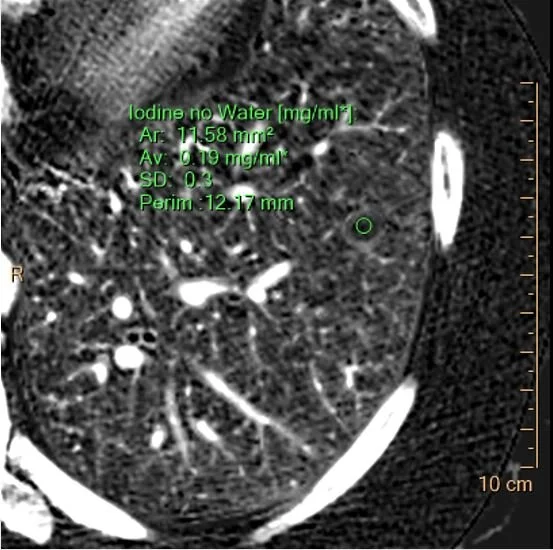

And no iodine uptake on measurement.